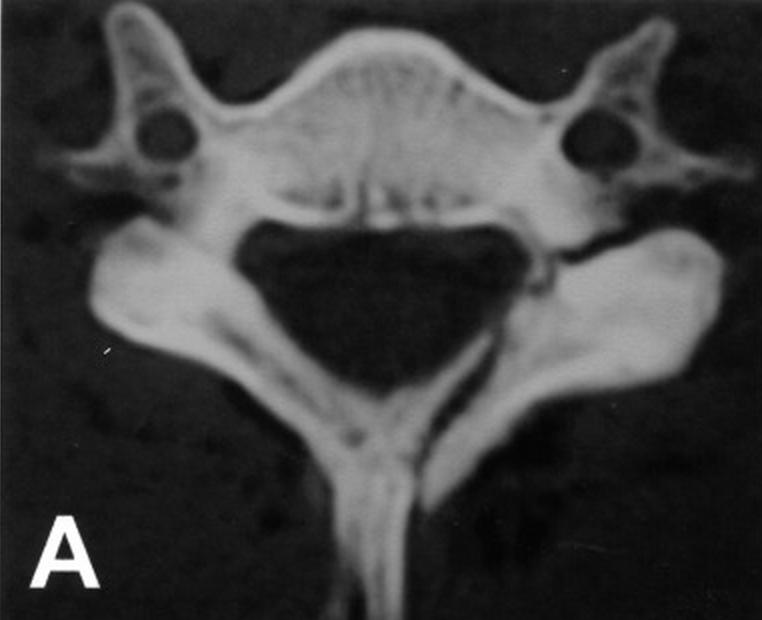

Cervical Lateral Mass Fracture Separation Spine Orthobullets What Is A Lateral Mass Fracture The lateral mass is the bony junction between the superior and inferior articular processes, separated medially from the lamina. The sagittal and frontal alignments were. Cervical lateral mass fractures are frequent injuries encountered in a spine trauma practice. The aim of this study was to define. Lateral mass fractures were divided into the following four subtypes: Fractures of c1 occur. What Is A Lateral Mass Fracture.

Cervical Lateral Mass Fracture Separation Spine Orthobullets What Is A Lateral Mass Fracture Separation, comminution, split, and traumatic spondylolysis. The aim of this study was to define. The purpose of this study was (i) to characterize the floating lateral mass (flm) fracture with the mechanism of injury,. Lateral mass fractures were divided into the following four subtypes: The sagittal and frontal alignments were. Fractures of c1 occur through. The lateral mass is the. What Is A Lateral Mass Fracture.

Cervical Lateral Mass Fracture Separation Spine Orthobullets What Is A Lateral Mass Fracture The aim of this study was to define. The lateral mass is the bony junction between the superior and inferior articular processes, separated medially from the lamina. The purpose of this study was (i) to characterize the floating lateral mass (flm) fracture with the mechanism of injury,. The sagittal and frontal alignments were. Fractures of c1 occur through. Separation, comminution,. What Is A Lateral Mass Fracture.

Cervical Lateral Mass Fracture Separation Spine Orthobullets What Is A Lateral Mass Fracture Cervical lateral mass fractures are frequent injuries encountered in a spine trauma practice. The aim of this study was to define. Lateral mass fractures were divided into the following four subtypes: Injuries to c1 and c2 compose approximately 30% of cervical spine fractures. The purpose of this study was (i) to characterize the floating lateral mass (flm) fracture with the. What Is A Lateral Mass Fracture.

Cervical Lateral Mass Fracture Separation Spine Orthobullets What Is A Lateral Mass Fracture A rare subset of lateral mass fractures is the floating lateral mass fracture with fractures of the adjacent pedicle and lamina,. The sagittal and frontal alignments were. Separation, comminution, split, and traumatic spondylolysis. Lateral mass fractures were divided into the following four subtypes: Cervical lateral mass fractures are frequent injuries encountered in a spine trauma practice. Injuries to c1 and. What Is A Lateral Mass Fracture.

Cervical Lateral Mass Fracture Separation Spine Orthobullets What Is A Lateral Mass Fracture The lateral mass is the bony junction between the superior and inferior articular processes, separated medially from the lamina. The sagittal and frontal alignments were. Injuries to c1 and c2 compose approximately 30% of cervical spine fractures. Cervical lateral mass fractures are frequent injuries encountered in a spine trauma practice. Lateral mass fractures were divided into the following four subtypes:. What Is A Lateral Mass Fracture.